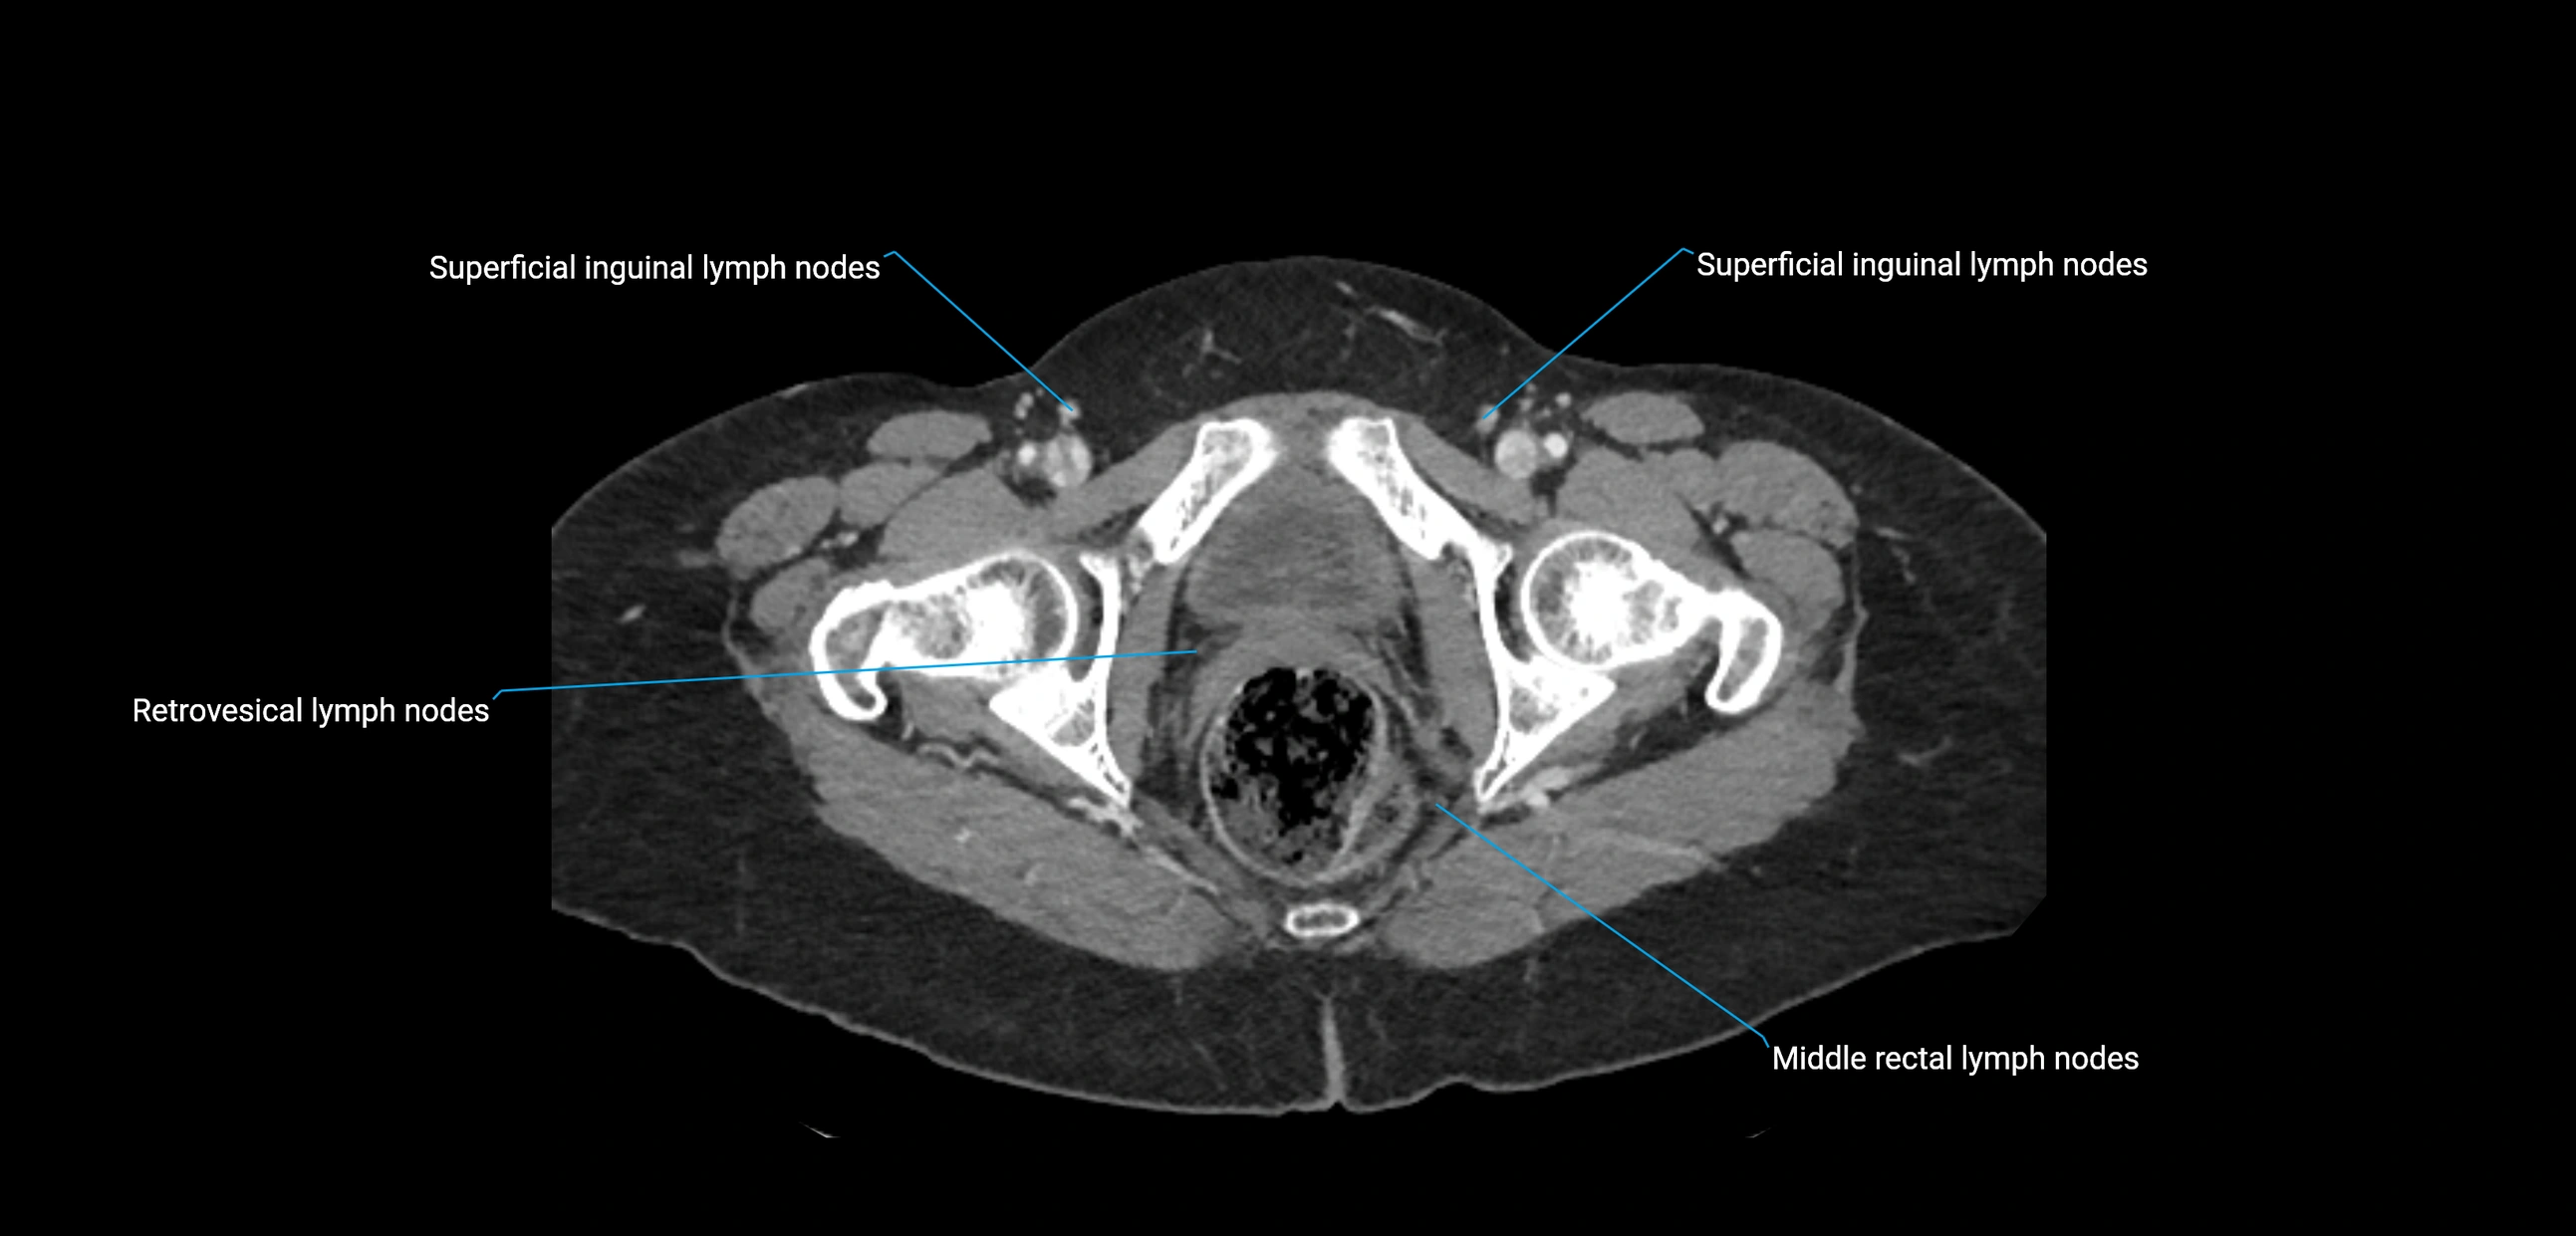

CT image

image